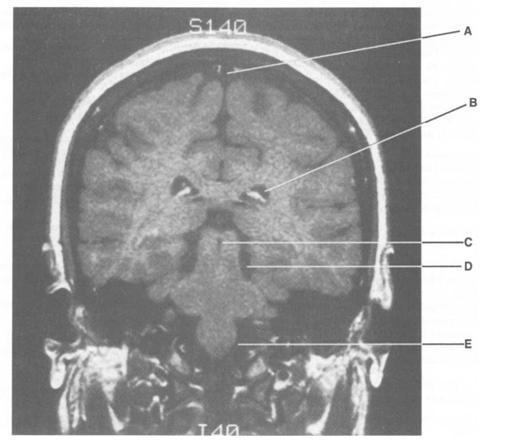

9

Q

Match with T-1 MRI

1. Superior cistern

2. Blockage results in hydrocephalus

3. Lateral ventricle

4. Contains the two foramina of Luschka

5. Receives cerebrospinal fluid (CSF) via the

foramen of Magendie

13-C. The superior (quadrigeminal) cistern overlies the dorsal aspect of the midbrain.

14-B. Blockage of the interventricular foramen of Monro (e.g., due to a colloid cyst of the third

ventricle) results in hydrocephalus involving the lateral ventricle.

15-A. The lateral ventricle is seen between the corpus callosum and the fornix.

16-D. The fourth ventricle contains the two foramina of Luschka that drain into the two cere-

bellopontine angle cisterns.

17-E. The cerebellomedullary cistern receives cerebrospinal fluid (CSF) via the foramen of Ma-

gendie.